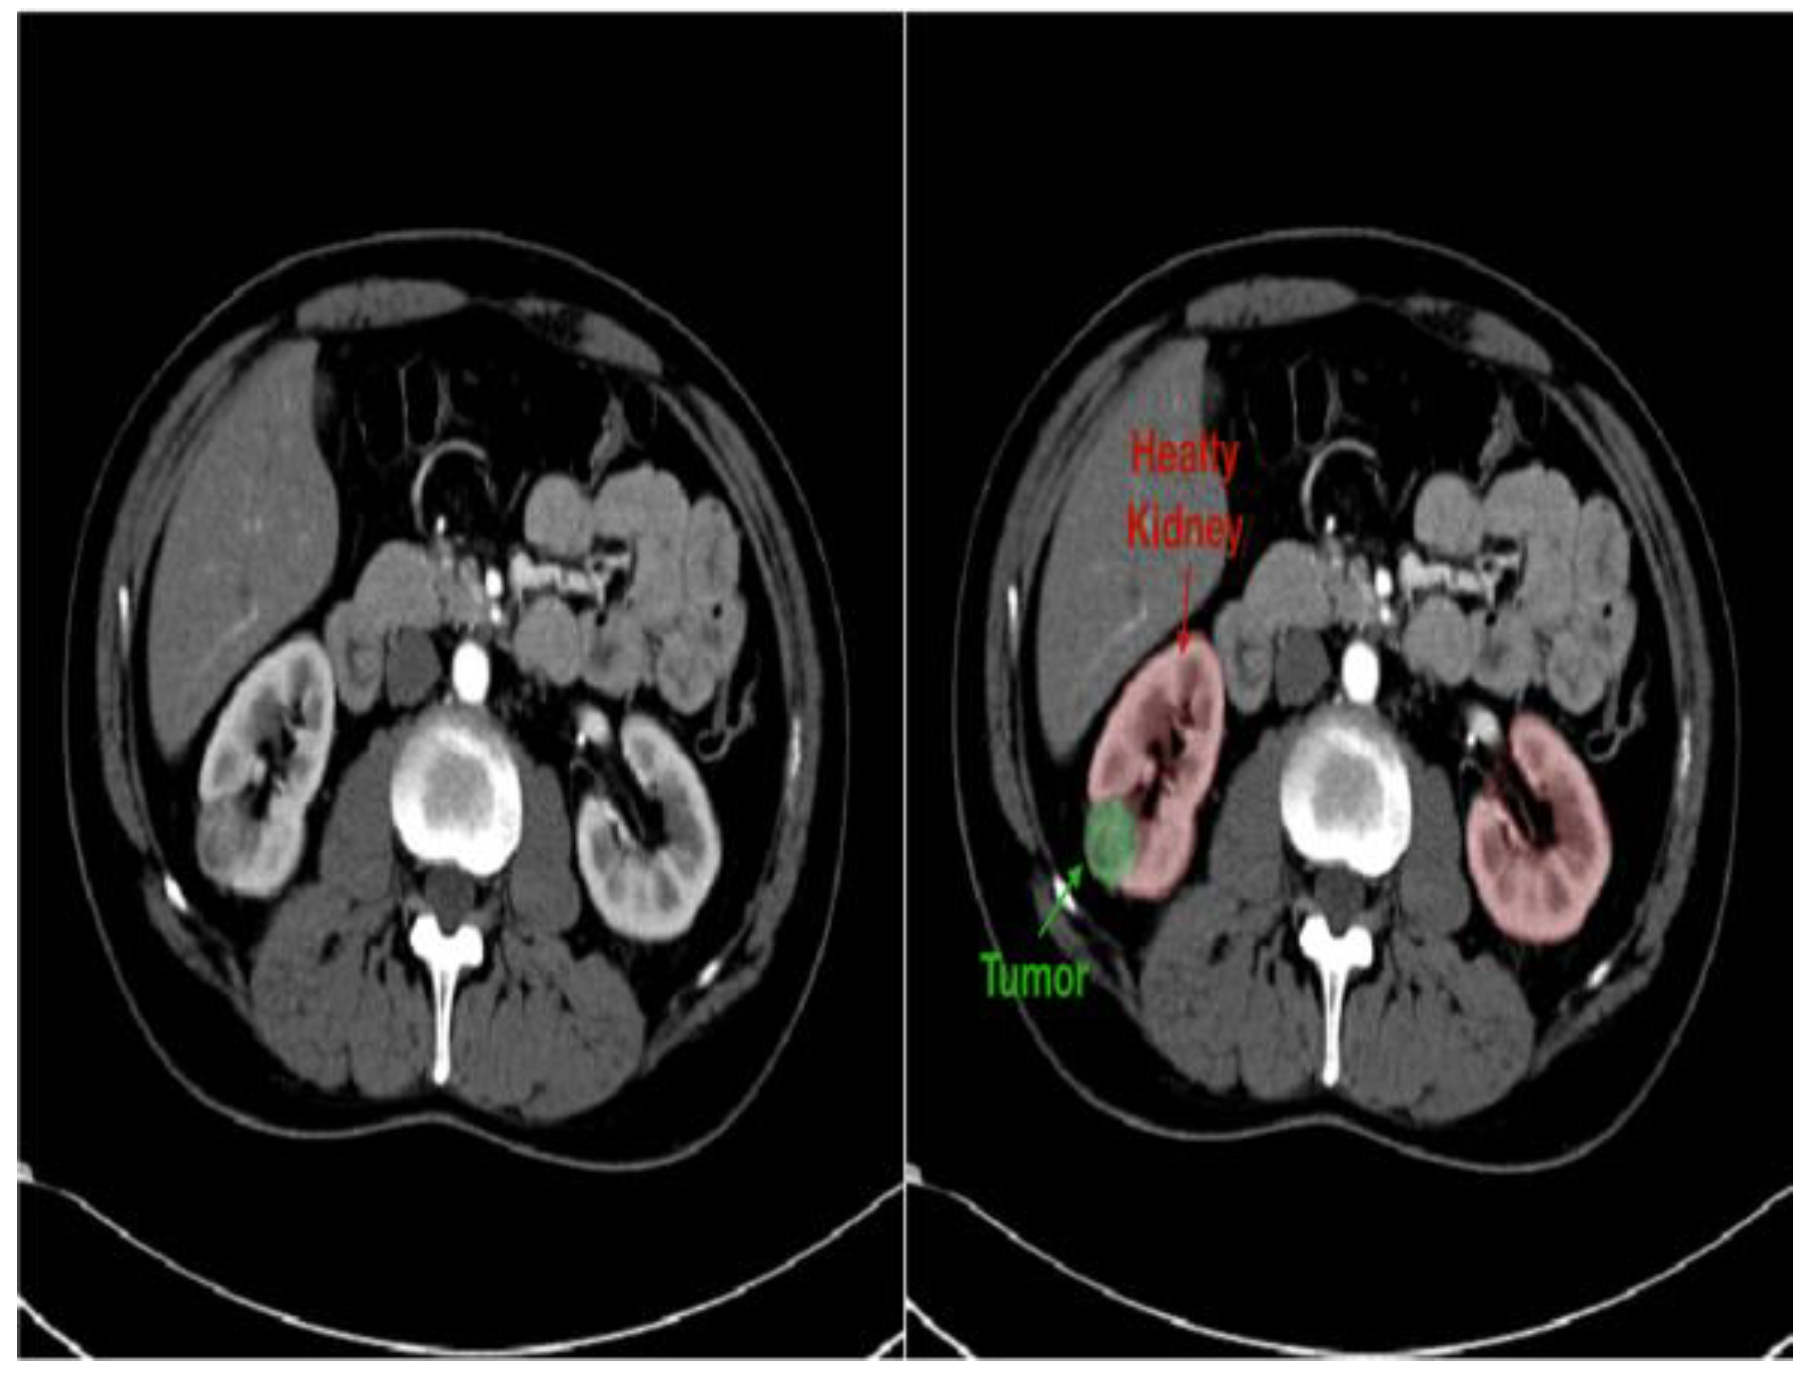

- Diagnostic difficulties: Children with kidney tumors and stones may exhibit nonspecific symptoms such hematuria, stomach discomfort, or urinary tract infections, which can be mistaken for other common pediatric ailments. Therefore, a combination of clinical evaluation, imaging exams, and laboratory investigations is crucial for accurate diagnosis. However, it can be difficult to differentiate between different forms of stones or distinguish between benign and malignant tumors, requiring a thorough diagnostic approach [39].

- Imaging modalities: A number of imaging modalities, such as intravenous pyelography (IVP), CT, MRI, and ultrasound, are essential for the diagnosis of juvenile kidney cancers and stones. Ultrasound is noninvasive and emits no ionizing radiation, so this method is used as a first-line imaging modality to examine renal morphology and identify structural problems (Figure 6). CT and MRI are more sensitive and specific for assessing stone load and identifying renal masses but also entail radiation exposure and require patient sedation [40].

- Treatment options: Tumor type, size, and location, and patient age are among the characteristics that influence how juvenile kidney tumors and stones are managed. Options for treatment vary from minimally invasive techniques and surgical intervention to cautious maintenance and attentive waiting. The primary therapy for kidney cancers that are localized is surgical excision; nephron-sparing techniques are recommended whenever possible in order to maintain renal function. Alternatively, depending on the size and composition of the stones, medicinal therapy, dietary changes, and minimally invasive techniques like ureteroscopy or shock wave lithotripsy (SWL) may be employed [41].

4.2.2. Pediatric Kidney Tumors

- Improved diagnostics: AI-driven image analysis tools can enhance the identification and description of pediatric kidney cancers and tumors. Radiologists can spot minor abnormalities, characterize renal masses, and estimate tumor burden more accurately using ML algorithms that have been trained on large datasets of pediatric renal images (Figure 7). AI algorithms enable the early identification of kidney cancers and tumors by methods including pattern recognition, masking, segmentation, and quantitative analysis, allowing for confident diagnosis and timely treatment [24].

- Personalized treatment planning: AI systems provide personalized therapy recommendations and perform the prognostic evaluation of patient-specific data, including clinical history, imaging results, and laboratory values. For young patients with kidney cancers, this customized strategy enables medical practitioners to maximize therapeutic efficacy, reduce treatment-related morbidity, and enhance long-term outcomes [43].

- Predictive modeling and risk stratification: AI predictive modeling enables doctors to identify children with kidney tumors who are more likely to experience treatment failure or disease progression. ML algorithms identify prognostic characteristics and biomarkers through the analysis of varied datasets. This improves treatment outcomes and survival rates for children with kidney cancers by empowering doctors to use tailored risk mitigation strategies and start treatment early [44].

- Ethical and regulatory considerations: Incorporating AI into the treatment of juvenile kidney cancers and tumors requires careful consideration to overcome legal, ethical, and practical challenges. Collaboration between developers, healthcare providers, and other stakeholders will be essential for ensuring the ethical and effective use of AI in clinical practice [45].